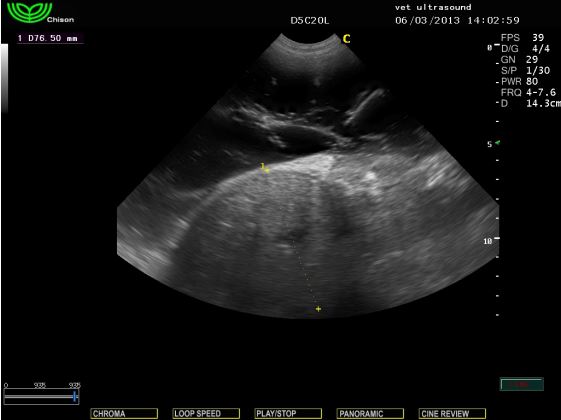

Στον υπέρηχο βρέθηκε ενδοκοιλιακή μάζα η οποία καταλάμβανε

όλη την κοιλιακή κοιλότητα και απωθούσε το λεπτό έντερο

Η μάζα αυτή ήταν ο όρχης ο οποίος είχε παραμείνει στη

κοιλιακή κοιλότητα και είχε εμφανίσει κακοήθη εξαλλαγή.